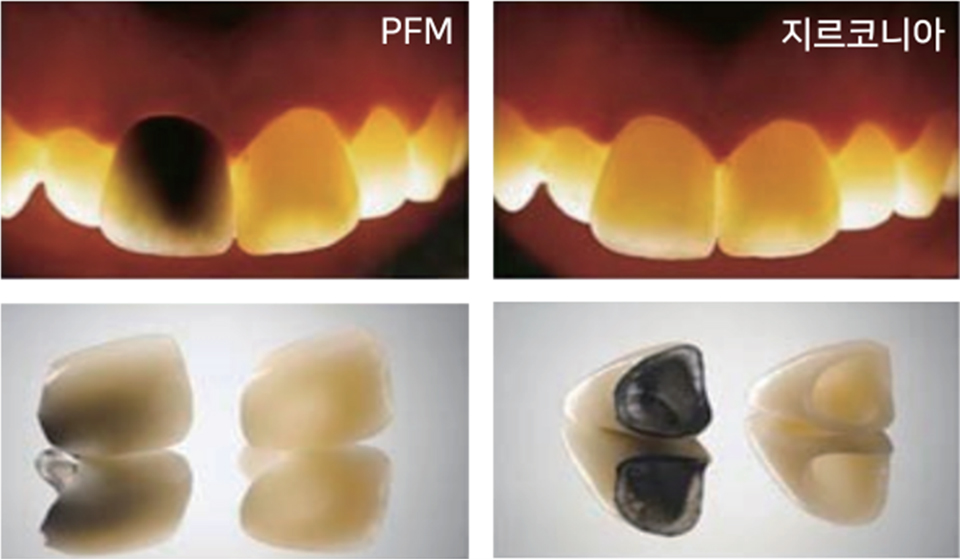

저렴한 비용으로 심미성도 잡는 PFM

VS

합리적인 비용으로 심미와 강도 모두 잡는 지르코니아

어두운 곳에서는 큰 차이가 느껴지지 않지만 빛이 비췄을 경우엔 큰 차이가 느껴집니다.

지르코니아와 달리 PFM은 빛이 비춰지면 안쪽의 메탈캡이 검게 보입니다. 이런점에서 PFM은 지르코니아에 비해 심미성이 떨어지는 재료로 앞니 등의 심미성이 요구되는 부위에는 부적합 합니다.